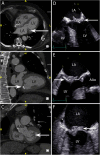

Infective Endocarditis (IE) remains a significant health challenge. Despite an increasing awareness, mortality is high and has remained largely unchanged over recent decades. Early diagnosis of IE is imperative and to assist clinicians several diagnostic criteria have been proposed. The best known are the Duke criteria. Originally published in 1994, these criteria have undergone significant modifications. This manuscript provides a timeline of the successive changes that have been made over the last 30 years. Changes which to a large degree have reflected both the evolving epidemiology of IE and the proliferation and increasing availability of advanced multi-modality imaging. Importantly, many of these changes now form part of societal guidelines for the diagnosis of IE. To provide validation for the incorporation of cardiac computed tomography (CT) in current guidelines, the manuscript demonstrates a spectrum of pictorial case studies that re-enforce the utility and growing importance of early cardiac CT in the diagnosis and treatment of suspected IE.